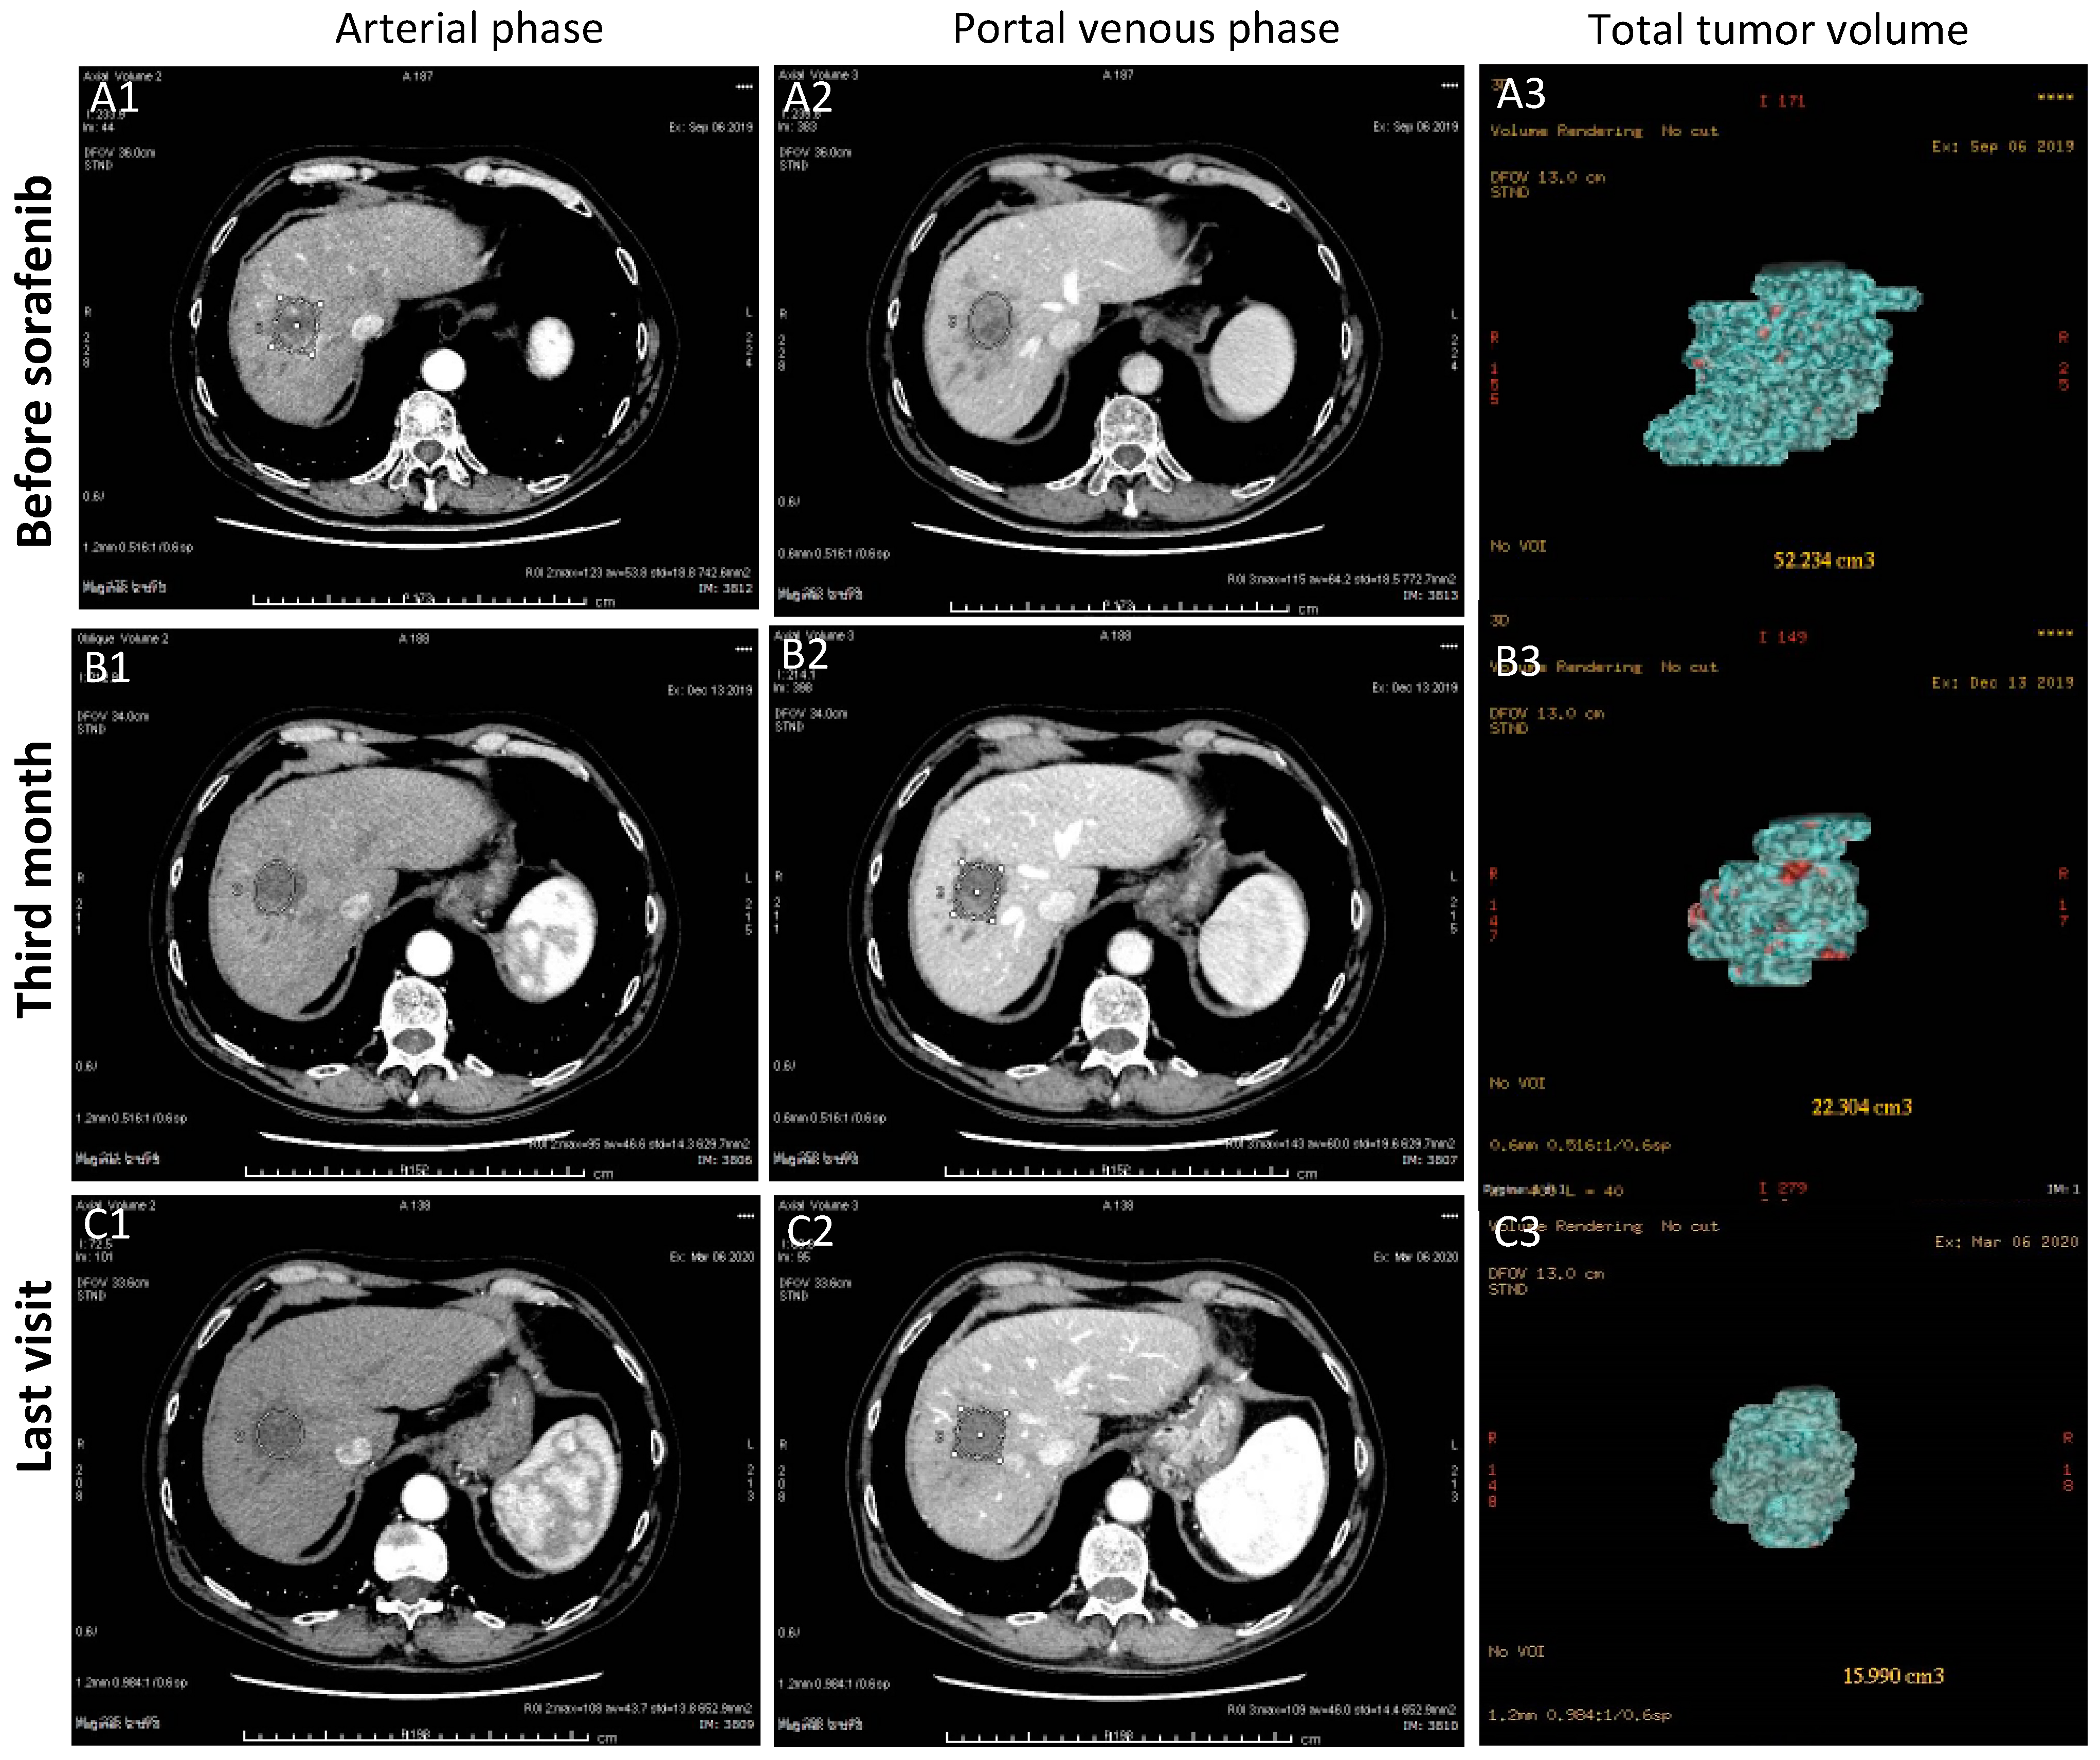

3.1.3. Case-3 (PR to Regorafenib)

| HCC volume (cm3) | 139 | 32 | 52.2 | 6.4 | 24.5 | 6.1 | 200 | 89 | 29.1 | 116 |

| Target Response * | CR | PR | PR | CR | CR | CR | SD | SD | PD | PD |